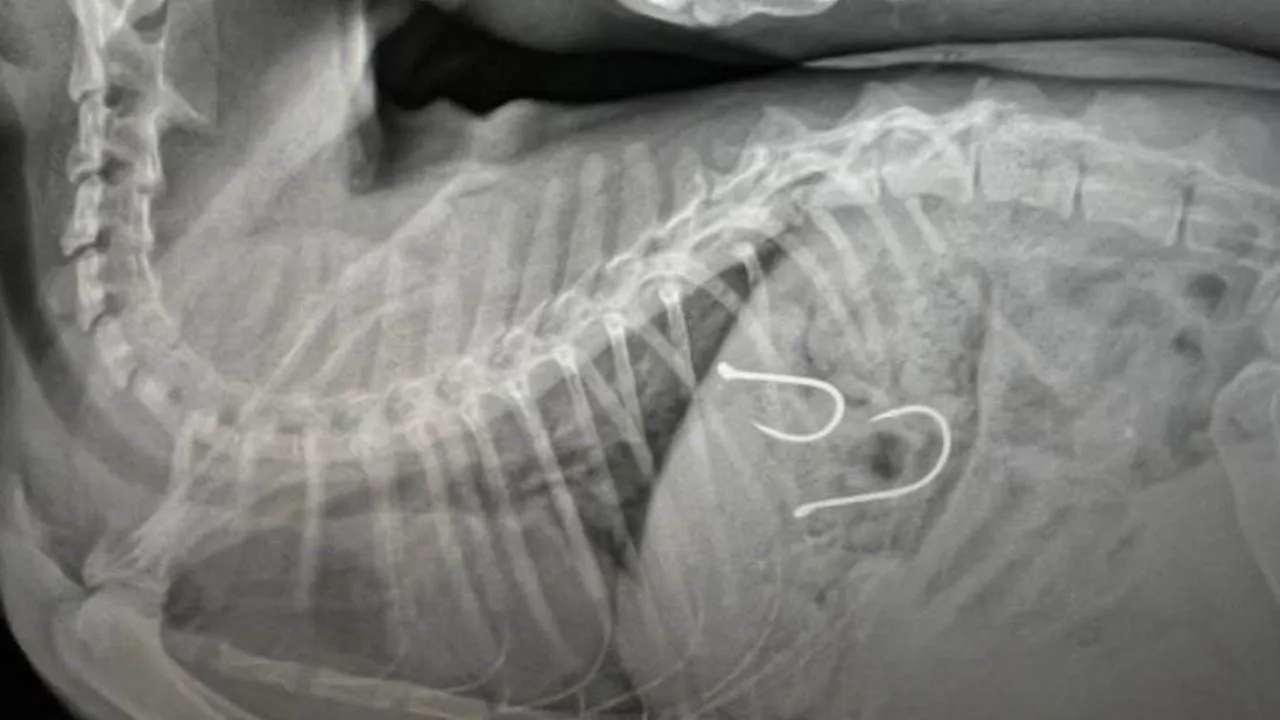

Sahil bandında dolaşan vatandaşlar, bir kedinin ağzından olta misinası sarktığını fark edince durumu Balıkesir Büyükşehir Belediyesi Sokak Hayvanları Tedavi Merkezi’ne ihbar etmişlerdi. Gelen ihbar üzerine kedi, ekipler tarafından müşahede altına alınmış ve sağlık durumu kritik olan yaralı hayvana acil olarak müdahale edilmişti. Çekilen röntgen sonucunda olta iğnelerinin kedinin midesine saplandığı anlaşılmış ve sonrasında ise kedi ameliyata alınmıştı.

Kedinin sağlık durumu ile ilgili Balıkesir Büyükşehir Belediyesi Sokak Hayvanları Tedavi Merkezi’nden edinilen son bilgilere göre, 2 adet olta iğnesi ve misinasının kedinin midesinden başarılı bir operasyonla çıkarıldığı, olta kancasının enfeksiyon oluşturma riskine karşı, antibiyotik ve serum tedavisine başlandığı belirtildi. Kedinin genel sağlık durumunda şu an için bir olumsuzluğun söz konusu olmadığı ve 48 saat yoğun bakımda tutulacağı aktarıldı.